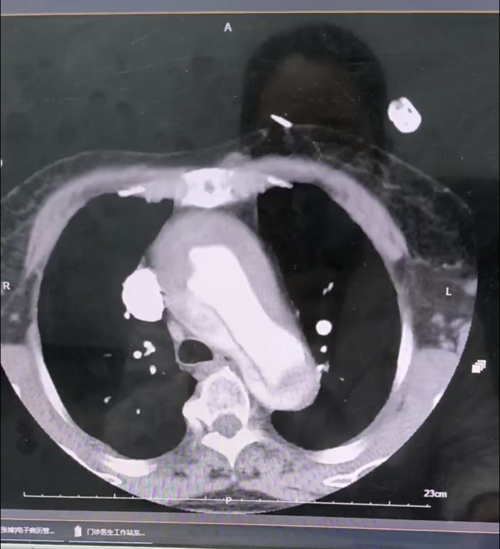

近日,84岁的李奶奶(化名)正在家中休息,突然感到一阵 "撕裂样"的胸背部剧痛,疼痛程度达到难以忍受的10级!家人立即将她送往邳州当地医院,经主动脉CTA检查确诊为 "主动脉夹层A型"——这个被称为"血管炸弹"的急症,死亡率高达每小时1%-2%!

更危急的是,进一步检查发现李奶奶还合并有冠心病(前降支重度狭窄),这意味着她的心脏随时可能因夹层破裂或心肌梗死而停跳。 "必须立即手术,但84岁高龄能否承受?" 带着这个疑问,家属决定转往徐州新健康心血管病医院进行治疗。

面对这位高龄的A型夹层合并冠心病患者,徐州新健康心血管病医院立即启动MDT多学科会诊,制定了 "一站式"手术方案,在麻醉科手术室输血科等相关科室配合下急诊行主动脉夹层A型孙氏手术+冠脉搭桥术。